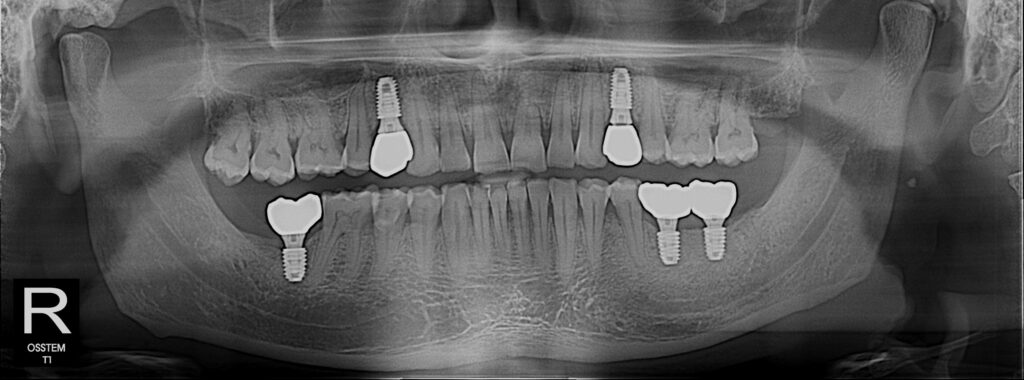

Full Mouth Dental Implant

Full mouth rehabilitation with implant supported bridge or denture always challenging. We have well trained surgical team lead by Dr Rahman and specialist prosthetic team to maintain up to mark quality and gaining chewing function. Options are All on 4 , Implant retained bridges and snap on denture.

Implant Gallery